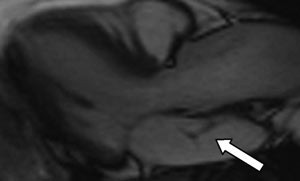

Som ledd i utredningen ble det utført transtorakal todimensjonal ekkokardiografi, som viste normale forhold, bortsett fra en mulig membran i venstre atrium som delte atriet inn i ett bakre og ett fremre kammer (fig 2).

Ved funn av membraner i venstre atrium er det viktig å bestemme de anatomiske forholdene for å kunne stille riktig diagnose. Differensialdiagnostisk er det særlig viktig å avgjøre relasjonen til aurikkelen. En supravalvulær mitralring er lokalisert apikalt for aurikkelen, mens en atriemembran (også kalt cor triatriatum sinister) er lokalisert basalt for denne. Venstre atrie-membran er en sjelden medfødt hjertefeil der en membran deler venstre atrium i to: Ett bakre kammer, som tar imot blod fra lungevenene, og ett fremre kammer, som kommuniserer med aurikkelen og venstre ventrikkel over mitralklaffen (2). Membranen er sannsynligvis et resultat av manglende resorpsjon av den felles lungevenen. En liknende tilstand kan forekomme i høyre atrium (3).

Transtorakal ekkokardiografi var ikke tilstrekkelig til å stille en sikker diagnose. Vi valgte derfor å gå videre med transøsofageal ekkokardiografi, som viste at membranen dekket en relativt stor del av atriet (fig 3). Det så ut til å være god passasje for blodstrømmen, siden det ikke var tegn til utvidelse av atriet proksimalt for membranen. Det var heller ikke andre tegn til obstruksjon, som tåkevirvler i den bakre del av atriet eller retrograd blodstrøm i lungevenene. Membranen var lokalisert basalt for aurikkelen. Det dreide seg dermed om en venstre atrie-membran.

Den transøsofageale undersøkelsen har betydelige fordeler fremfor den transtorakale når det gjelder strukturer i atriene, pga. av fysiske begrensninger ved ultralydteknologien. Hos denne pasienten kunne transøsofageal ekkokardiografi bekrefte diagnosen og belyse betydningen av membranen for blodstrømmen.